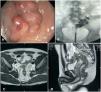

Un hombre de 36 años, sin antecedentes médicos ni quirúrgicos previos, fue evaluado en la sala de urgencias. Presentaba rectorragia, diarrea acuosa, fecaluria, neumaturia y pérdida de 12?kg de peso. El examen físico fue normal y la tomografía computarizada abdominal mostró un crecimiento difuso del recto medio y superior, infiltración de grasa perirrectal, ganglios linfáticos crecidos (>7mm), sin enfermedad metastásica. La colonoscopia inicial mostró un tumor obstructivo a 7cm de la unión anorrectal. Al día siguiente se realizó una colostomía sigmoidea en asa de derivación. El antígeno carcinoembrionario (CEA, por sus siglas en inglés) estaba elevado (11.4 ng/ml) y, dada la historia de fecaluria y neumaturia, se realizó una cistoscopia, con la que se documentó un orificio de 2mm, compatible con fístula. A continuación, un fistulograma demostró que el paciente tenía cáncer rectal en etapa IIIC (T4bN1M0), complicado por una fístula rectovesical. Las biopsias mostraron adenocarcinoma rectal y la inmunohistoquímica reportó ausencia de inestabilidad microsatelital. Una imagen de resonancia magnética (RM) identificó un tumor que infiltraba la pared posterior de la vejiga y 3 ganglios linfáticos sospechosos (fig. 1).

A) Colonoscopia que muestra una masa rectal que obstruye el 100% del luz, localizada 7cm arriba del borde anal. B) Fistulografía realizada por medio de cistoscopia que muestra contraste en la porción distal del colon sigmoideo y el recto superior. C-D) Imagen por resonancia magnética T2 inicial que muestra un tumor en contacto con la pared posterior de la vejiga urinaria.